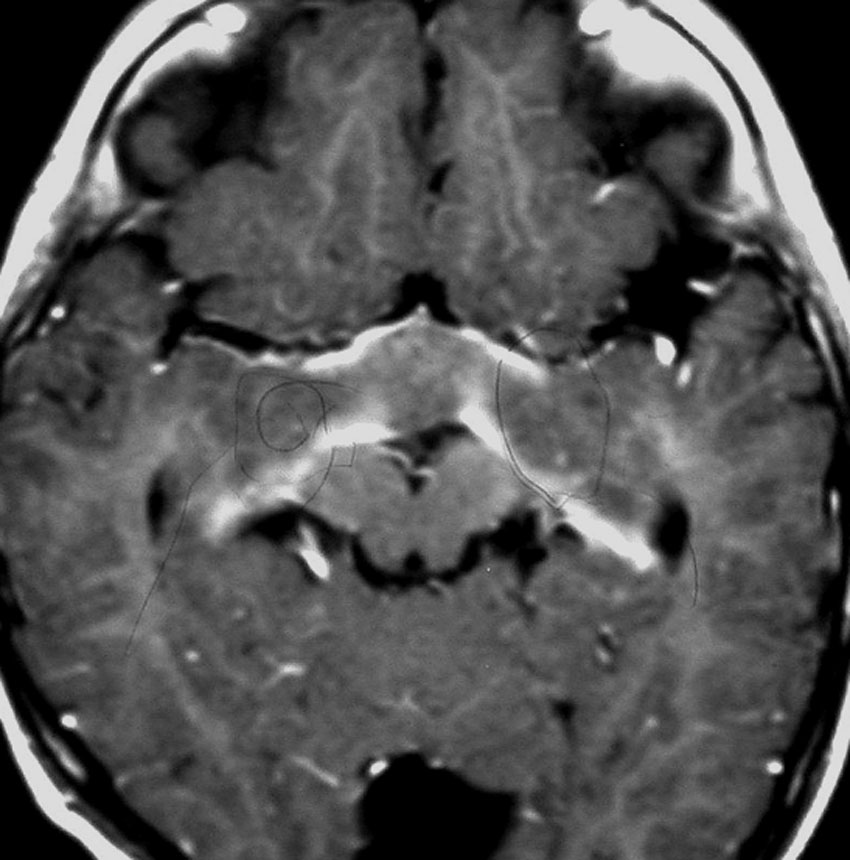

化学療法が有効なのは,上の画像のようにガドリニウム増強で強く増強されるタイプです,またT2強調画像で強い高信号になるものほど化学療法が有効です,要するに毛様粘液性星細胞腫の要素に化学療法が有効であるということです

この毛様細胞性星細胞腫はガドリニウムでほとんど増強されません(右側のMRI)から,化学療法を行っても小さくなりませんので,手術摘出する必要があります,実際に視床下部から発生したもの視交叉が犯されておらず,手術亜全摘出できました